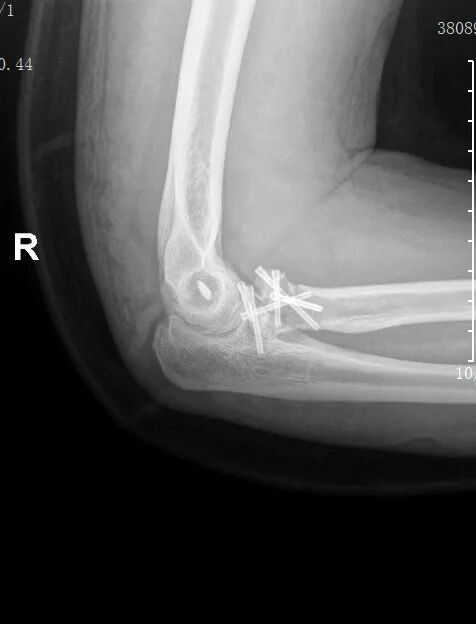

黄益平主任接诊后,经详细询问病史、查体并完善相关检查后,明确诊断为 “右肘关节恐怖三联征( 右尺骨冠突骨折、右桡骨小头粉碎性骨折 、肘关节后脱位已复位)”。

患者术前影像

恐怖三联征

“恐怖三联征, 是肘部最复杂的高能量创伤之一 ”,黄益平主任介绍,该病症因涉及骨性结构与软组织的复合损伤, 治疗难度极大, 若处理不当易导致关节僵硬、不稳定、创伤性关节炎等后遗症,甚至可能造成永久性功能障碍。